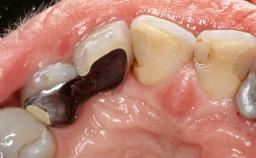

Reconstructive Treatment of a Peri-Implantitis Defect at an Implant in a Mandibular Molar Site

In this case, Mario Roccuzzo utilizes surgical bone regeneration treatment around implant 46 using a bone graft substitute and a connective tissue graft to resolve peri-implant inflammation, reduce the probing depths, and prevent further progression of disease.

A 58-year-old-male patient was referred in February 2007 for implant placement in the right mandibular molar area. Two tissue level implants were inserted at sites 44 and 46, respectively, to support a three-unit fixed dental prosthesis (FDP).